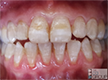

At tooth level, a newly-erupted Hypomin Molar will typically exhibit:

- one or more "demarcated opacities", being spots or patches of opaque enamel with abnormal colour (white, cream, yellow or brown) and distinct boundaries with normal enamel

- such opacities have normal thickness of enamel throughout, but this may not last for long

- likewise the opacity surface is initially intact, but this may not last for long as pictured here for a severely Hypomin 6-year molar undergoing "eruptive breakdown" while it's still erupting

- demarcated opacities are usually located in the cuspal half of the

crown and, where multiple opacities appear on a single tooth, they

may vary in colour, size and shape - Hypomin Molars may also elicit a painful response to mild stimuli